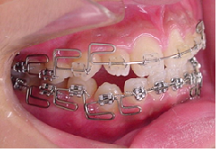

当院の治療では、上顎から矯正装置を装着していきます。

その後下顎の矯正装置を装着します。

この過程で歯並びが整いMEAW(マルチループ)を装着しやすくなります。

MEAW(マルチループ)を使用する事で、上顎前突(出っ歯)や咬合高径(咬み合わせの高さ)の改善をしています。

☆治療途中